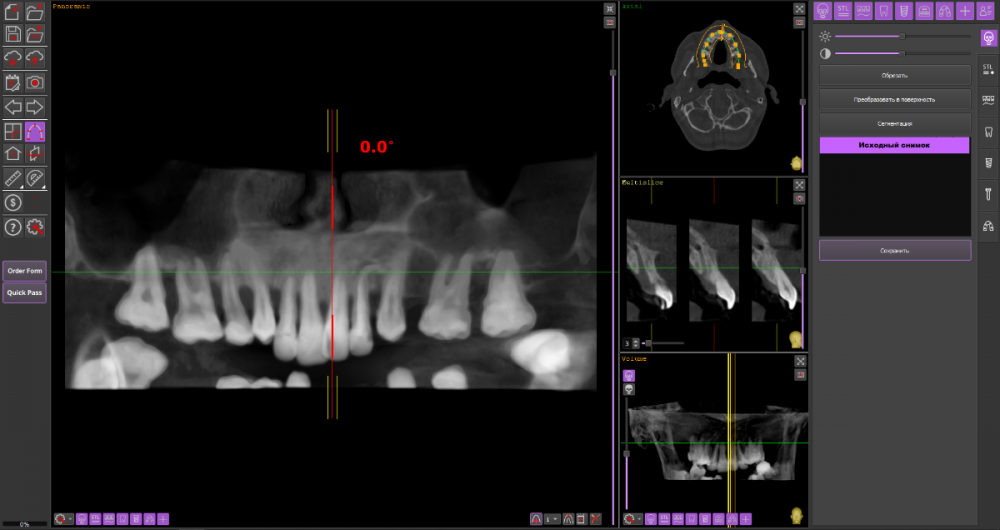

Сергей34 Опубликовано 5 ноября, 2022 Поделиться Опубликовано 5 ноября, 2022 Уважаемые доктора, надеюсь на ваше понимание - дело возможно для вас обыденное, пациенту очень сложно. Мне 34 года. Вот ссылка на архив с 3 д кт. https://drive.google.com/drive/folders/1sEpt1GplfkE7_Y9vTtyIFoQWssskl3XU?usp=sharing Кратко про истории болезни, недоразвитвая нижняя челюсть, неправильный прикус, пародонтит с самых юных лет. Итого в 34 года я продолжаю терять зубы - условно здоровые, альвиола убывает. Насколько мне обьяснили врачи в реале, на нижнюю челюсть можно поставить 6 имплантов без подсадки кости. На верху только с синусом (синус не потяну, слишком дорого обходится для меня). Без синуса только 4 импланта можно установить. Изначально я думал протезировать пока только низ, а верх оставить на потом. Но как мне обьяснили опять таки это будет риском для нижних конструкций, тем более учитывая активную убыль кости на верхней челюсти это лишь дело времени - не столь отдалённого, но там может оказаться так что и эти 4 импланта будет затруднительно поставить из за продолжающейся убыли. Врач мне сказал что при состоянии моих десён, ставить импланты сразу нельзя - нужно удалив все зубы подождать восстановления связок, ран 8 недель, после чего поставить импланты и дать им прижиться 3 месяца. А моя работа связанна с переговорами, если я не говорю я не работаю = теряю приток средств на эти манипуляции. Я чисто физически не могу себе позволить так долго находится вне рабочем состоянии. Итого у меня 2 вопроса на которые я конкретные ответы так и не смог получить от докторов; 1.Возможно ли изготовить и носить (будут ли держаться) простые съёмные протезы спустя 15 дней к примеру после удаления зубов ( в рабочее время 4-5 ч в день) не используя их для употребления пищи? Сильно ли это ношение отрицательно сказывается на восстановлении для дальнейшей имплантации? 2.С нижней челюстью на первый взгляд всё понятно, туда возможно на 6 имплантов установить метало-керамику из 12 зубов. А что с верхом? На 4 импланта ставить условно-сьёмный протез тем более что мне всего 34 года, как я понимаю эта конструкция не слишком надёжна всю нагрузку распределять всего на 4 импланта? Альтернативой может являться сьёмный протез на балке или без балки? Из акрила например или какой ещё материал возможен? Чтобы они с протезом нижней челюсти (к примеру метало-керамикой) друг друга не перетёрли ? 3.Главный вопрос учитывая склонность десён к пародонтиту, даже если убрать все зубы (пусть даже с правильной гигиеной), имеются шансы что болезнь будет вокруг имплантов продолжать свои злоключения - стоит ли эта игра всех этих трат? Или дешевле и проще будет поставить на низ 2 импланта и на верх 2 импланта и сделать на них протезы? И терять потом если что будет не так накладно по деньгам. Прошу помочь консультацией. Очень требуется по человечески помощь, я так сильно запутался что не знаю что делать просто и порой единственным решением кажется просто удалить остатки зубов и сделать простые сьёмные протезы. Всем кто зайдёт в тему, найдёт или не найдёт даже время высказать мнение - заранее благодарен. Ссылка на комментарий